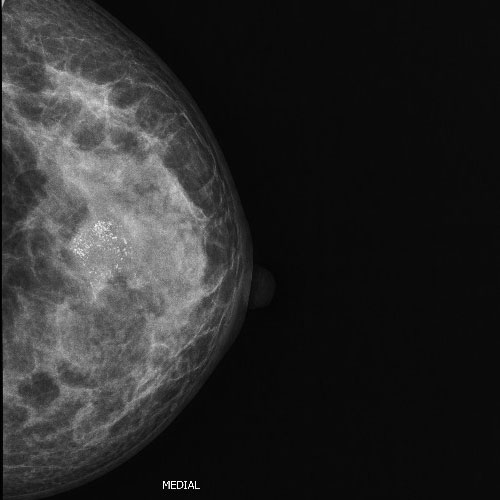

43 year old female with lump in left breast. Mammogram showing mass with scattered microcalcifications within the mass.